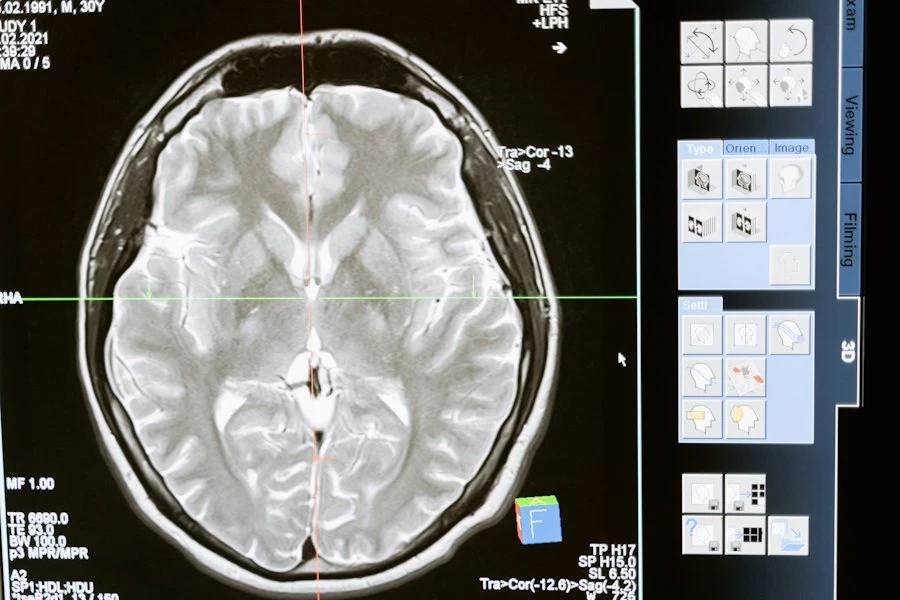

В эксперименте приняли участие 30 здоровых добровольцев обоих полов в возрасте от 22 до 40 лет. Испытуемым вводили изофлуран — популярный ингаляционный анестетик, используемый во всем мире. Ученые следили за изменениями мозговой активности с помощью электроэнцефалографии (ЭЭГ), фиксируя показатели как во время действия наркоза, так и после его завершения.

Результаты оказались весьма показательными. Женщины начали реагировать на слуховые сигналы в среднем через 29 минут после прекращения подачи анестетика. Мужчинам для этого потребовалось 45 минут. Более того, женщины быстрее восстанавливали скорость и точность в когнитивных тестах, что свидетельствует о более быстром восстановлении функций мозга.